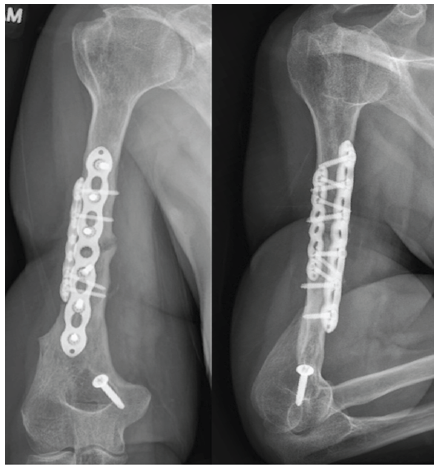

The previously harvested tibial bone graft was then mixed with cancellous chips and placed around the non-union site. The skin and subcutaneous tissues were closed and the patient was placed into a sling. The patient was admitted postoperatively and discharged in stable condition. The bone biopsy was read as benign bone and final bone cultures remained negative. The patient was initially made partial weight-bearing to graft donor site leg with plans to keep this limitation for 6 weeks postoperatively. However, the patient returned on her first clinic visit 2 weeks postoperatively ambulating without assistive device. The patient was seen in clinic routinely with radiographs at each visit and by her 9-month post-operative clinic visit, the cortical graft incorporated, and bony callus was apparent on radiographs (Fig. 5). The patient regained pain free range of motion that was symmetric to the contralateral side (Fig. 6.)

Figure 5: Post-operative anteroposterior and lateral radiographs at 9 months post-operative clinic visit; post-operative anteroposterior and lateral radiographs 9 months after humeral shaft non-union takedown and open reduction and internal fixation.